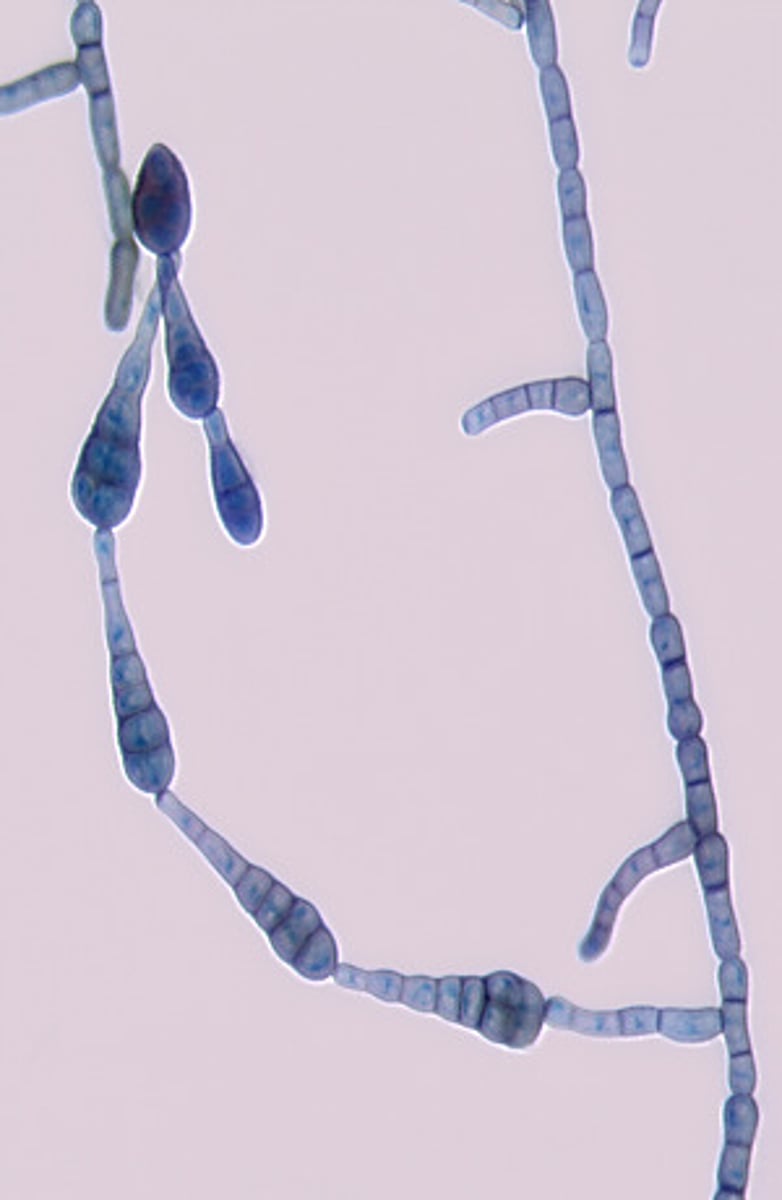

This microscopic image suggests which of the following dermatophytes?

Microsporum canis

Microsporum canis produces rough, spindle-shaped, thick-walled macroconidia.